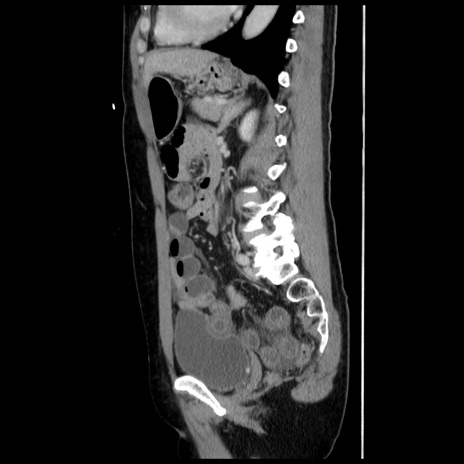

症例10(矢状断像)

【症例】 50歳代女性

【主訴】 腹痛

【現病歴】前日生レバーを食べた。今朝に排便あり。 昼前に突然発症の腹痛を生じ、当院救急外来を受診した。

【既往歴】 子宮筋腫にてで子宮全摘後

【身体所見】 意識清明、腹部:平坦、軟、下腹部やや左を中心に圧痛・反跳痛あり、筋性防御あり

【データ】WBC 7800、CRP 0.07